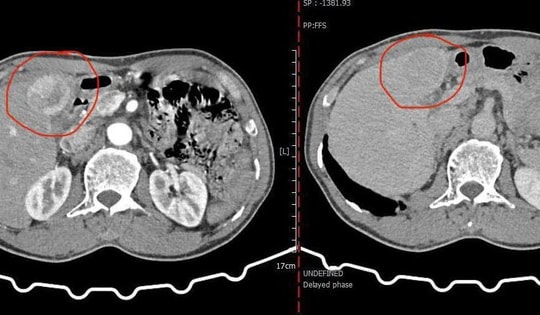

Tưởng đã khỏi viêm gan sau 20 năm, người đàn ông bất ngờ phát hiện ung thư gan di căn

Bệnh nhân 53 tuổi bàng hoàng phát hiện khối u gan 61mm đang di căn sau 2 thập kỷ không theo dõi bệnh viêm gan. Ca bệnh là hồi chuông cảnh báo cho những ai đang chủ quan với sức khỏe lá gan.